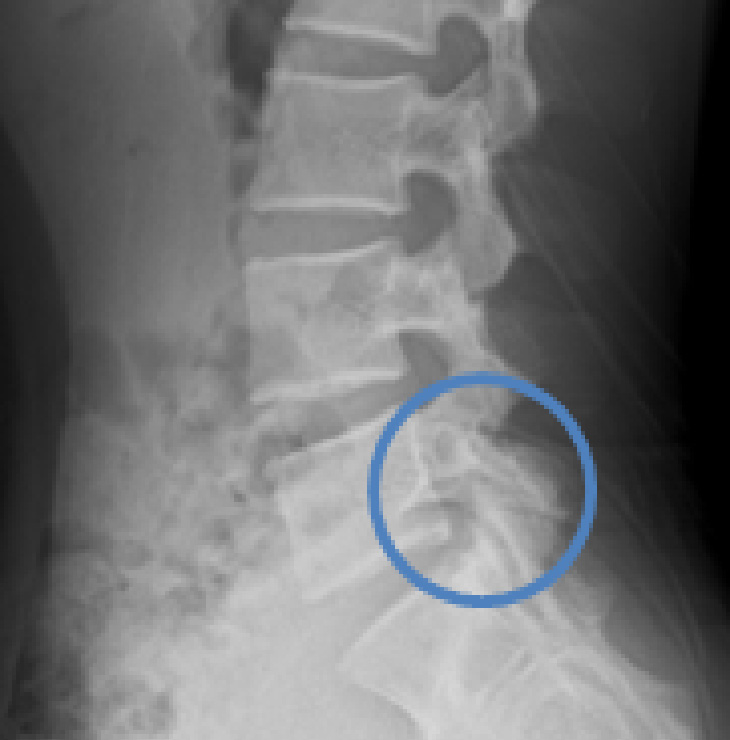

成長期腰椎分離症

成長期腰椎分離症とは

成長期腰椎分離症はスポーツにおける腰部障害の中で頻発しやすい疾患の一つです。病態としては、繰り返される腰椎への伸展、回旋ストレスが関節突起間部に集中し、疲労骨折を起こす事とされています。症状としては他の腰痛症と同じような腰痛が発生するため、鑑別には画像所見が必要とされています。

・レントゲン、CT、MRIを用いて分離部位や骨癒合の状態を確認します。

・MRIは初期分離の早期発見に有用です。